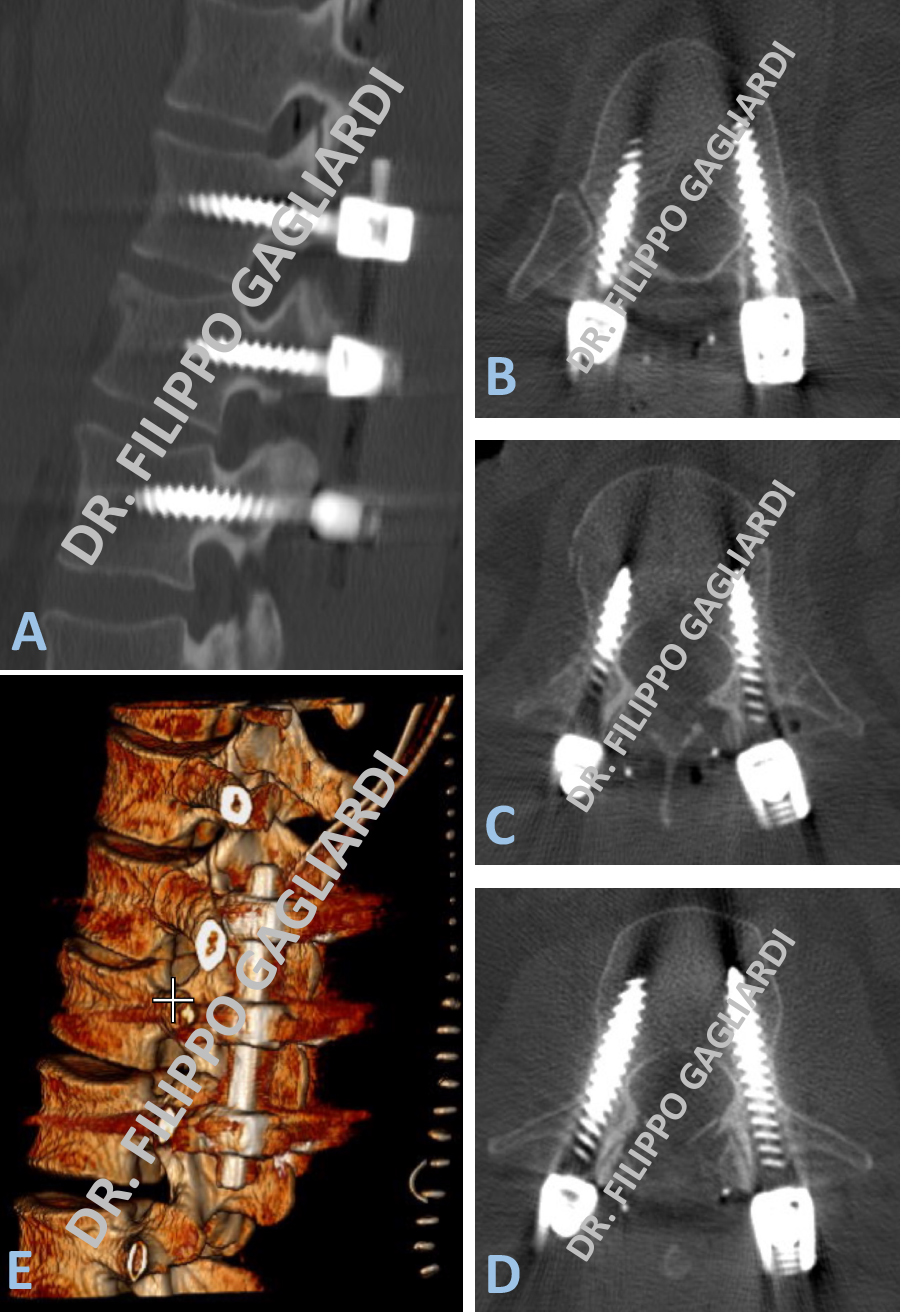

Patologia malformativa spinale Caso di paziente con tethered cord (midollo fissato) (midollo spinale fissato da un cordone fibroso a livello dell’osso sacro) associato ad un lipoma intradurale (tumore benigno di tessuto adiposo) a livello delle ultime radici spinali che presiedono al controllo degli sfinteri (freccia azzurra, Figura A).

È una condizione in cui il midollo spinale rimane ancorato verso il basso da un cordone fibroso (filum terminale) che lo stira verso il basso e ne causa sofferenza. In condizioni di normalità il midollo spinale termina a livello della prima vertebra lombare (cono midollare), nel caso presentato il midollo termina a livello della quinta vertebra lombare, perché stirato verso il basso. La paziente si presentava in ospedale per incapacità ad urinare (ritenzione urinaria) e perdita di feci (incontinenza). Veniva sottoposta ad intervento di disancoraggio midollare (sezione del cordone fibroso) e decompressione delle radici nervose mediante asportazione sub-totale del lipoma. L’intervento veniva eseguito sotto monitoraggio neurofisiologico per preservare la funzione dei nervi. La RM post-operatoria (Figura B) dimostra gli esiti dell’intervento con riduzione significativa del lipoma e detensione dei nevi e del midollo spinale (freccia rossa, Figura B). Nel post-operatorio si è assistito ad un miglioramento della funzione sfinterica della paziente.